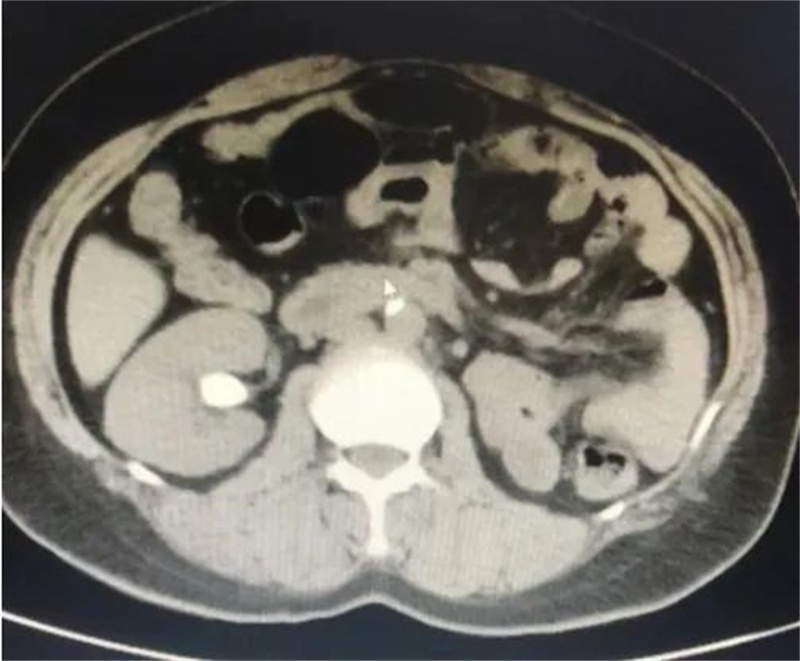

万般绝望之际,王女士多方打听,在朋友的推荐下来到徐州市中医院泌尿外科就诊。入院后,经CT检查显示,王女士右肾下盏结石,直径为2.1*1.6cm,结石CT值1360Hu,初步判断为草酸钙结石。

右肾结石(术前)